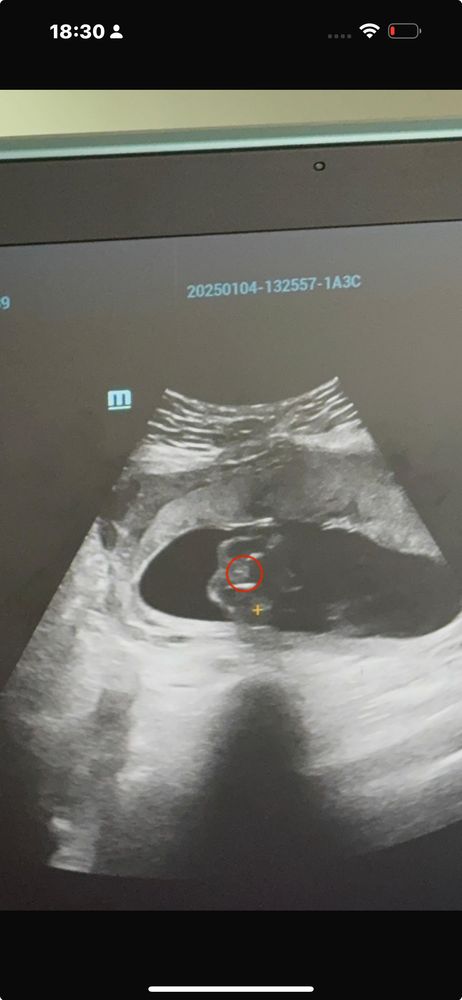

Девочки помогите🥹🙏

По моему на нижнем фото вы ножку обвели 😃 а на первом непонятно. Мне в 13, 16 недель говорили мальчик сто процентов, так и есть. В 19 недель показали четко как выглядит наше отличие) и на 2 скрининге в 21 неделю тоже показали) если узист на таком сроке не может рассмотреть из-за того, что малыш прикрыл, то предполагать бессмысленно, тут вот именно что гадать кому что покажется)

Лимоночка, в 13,16 и вот фото которые приложила в 20 недель предполагали мальчика. Вчера было ровно 26 недель и малыш прикрыл. А я до сих пор на 100% не знаю кто у нас 😄

Могу ошибаться конечно,но мне кажется это мальчик🙈

14 недель. Помогите определить пол =) Пол ребенка